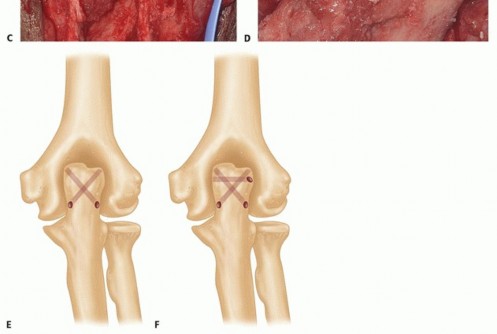

TECH FIG 6 •(continued)C,D. The triceps footprint to which reattachment should be attempted is predominantly on the flat part of the ulna or olecranon process, and not the tip, which is resected to prevent posterior abutment. E. Drill holes (1.5 to 2 mm) are oriented in a crossing fashion to secure the triceps to the footprint area. F. A separate cinch suture is used to increase the security and the area of contact between the triceps and the ulna, thereby improving healing potential.